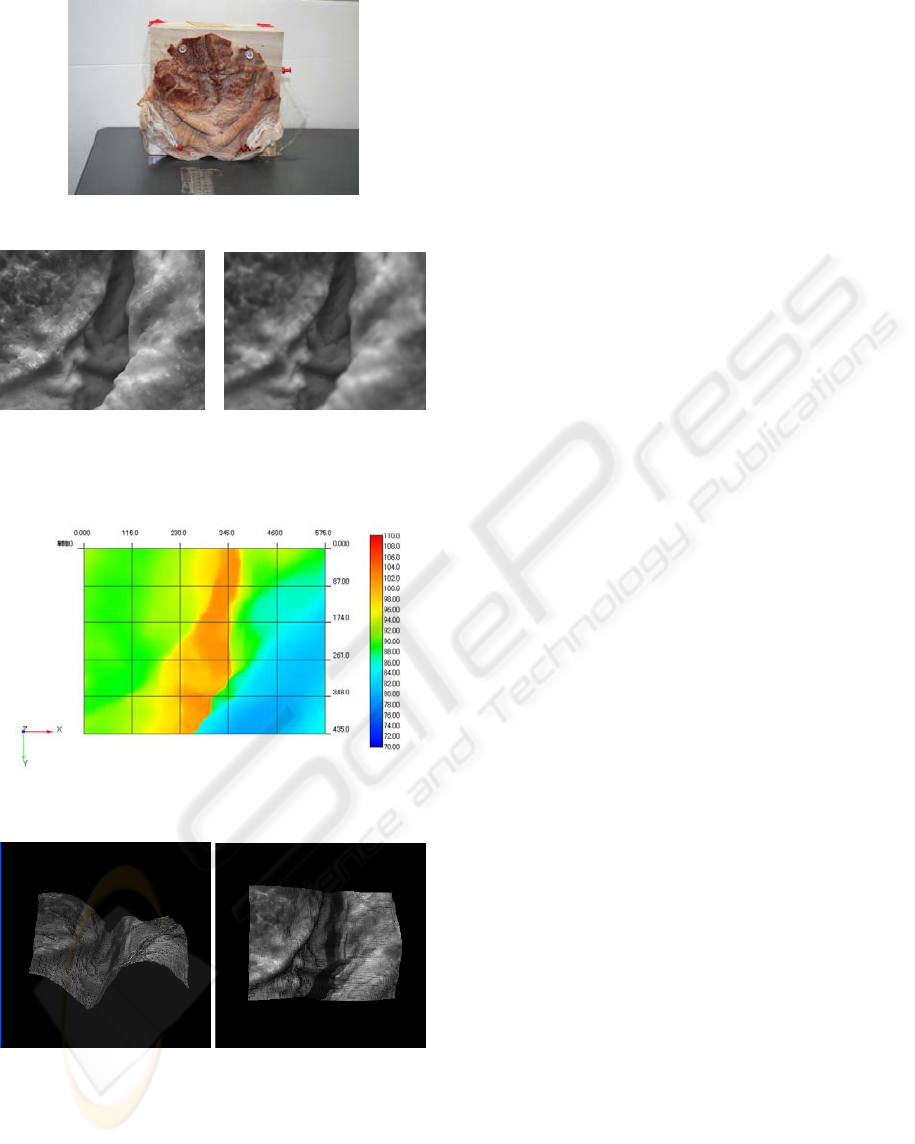

We propose a configuration for 3-D shape

recovery of endoscopic images based on shape from

focus (SFF). Figure 1 is a schematic diagram of

concept of our method. In SFF method, shape is

obtained with the use of the image sequence

partially in-focus taken by changing the focused

position. The analysis of focus to estimate depth

The steps of SFF process are following. First, two or

more pictures are taken by changing the image

sensor position, the lens position or the object

position. In this paper, lens position is varied for

image sequence. Second, the focus measures of each

pixel in the each image are compared, and the

camera parameters are estimated by which the

photographed object is perfectly focused. Finally,

we can obtain the depth of each point from the

camera parameters.